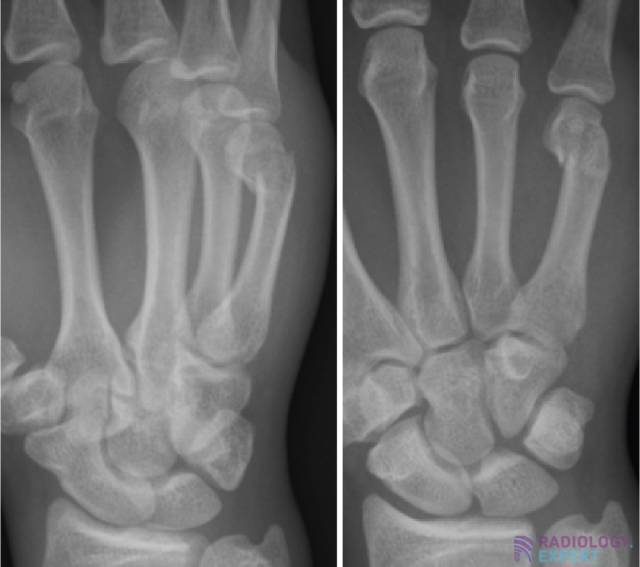

Boxer’s fracture. Boxer’s fracture.